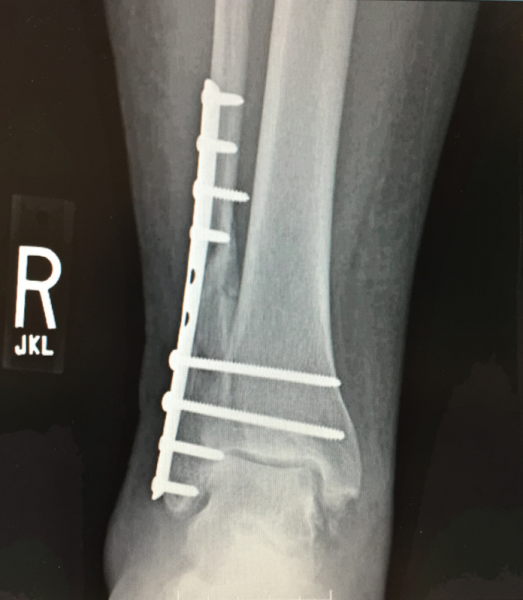

She had surgery on Dec. 1, the Tuesday of RSNA 2015. The orthopedic surgeon practiced at Elmhurst Hospital in Elmhurst, Ill., across the county from Naperville. But, thanks to the remote image viewing system, they could get the ED images for reference and planning. The surgeon’s post-surgery DR image showing the reconstruction of the fibula also was available via my mom’s patient portal. (Figure 4)